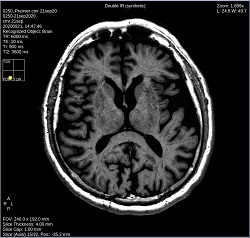

- By default, a 6-viewport display is launched with 6 unique MAGiC images.